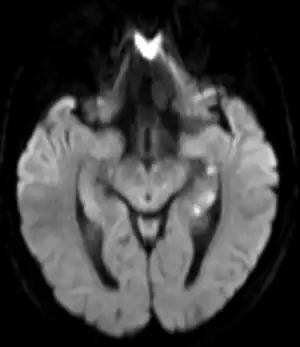

.png.webp)

Unless there are concerning features, limited testing is required.[1] Medical imaging and lumbar puncture are generally not required.[1]

Recently, moreover, both imaging and neurocognitive testing studies question whether TGA is as benign as has been thought. MRI scans of the brain in one study showed that among people who had experienced TGA, all had cavities in the hippocampus, and these cavities were far more numerous, larger, and more suggestive of pathological damage than in either healthy controls or a large control group of people with tumor or stroke.[15] Verbal and cognitive impairments have been observed days after TGA attacks, of such severity that the researchers estimated the effects would be unlikely to resolve within a short time frame.[16] A large neurocognitive study of patients more than a year after their attack has shown persistent effects consistent with amnestic mild cognitive impairment (MCI-a) in a third of the people who had experienced TGA.[37] In another study, "selective cognitive dysfunctions after the clinical recovery" were observed, suggesting a prefrontal impairment.[13] These dysfunctions may not be in memory per se but in retrieval, in which speed of access is part of the problem among people who have had TGA and experience ongoing memory problems.[12]